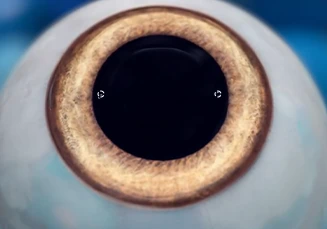

중앙의 작은 구멍을 통해

자연스러운 방수 흐름이 가능해

홍채 절개술이 필요하지 않아

회복이 빠릅니다.

방수의 원활한 흐름으로

수월하게 영양을 공급할 수

있어 홍채 절개 술의

부작용을 감소시킵니다.

원뿔형태의 중앙 홀을

원뿔형으로 제작함으로써

렌즈 아래의 방수 흐름을

원활하게 합니다.